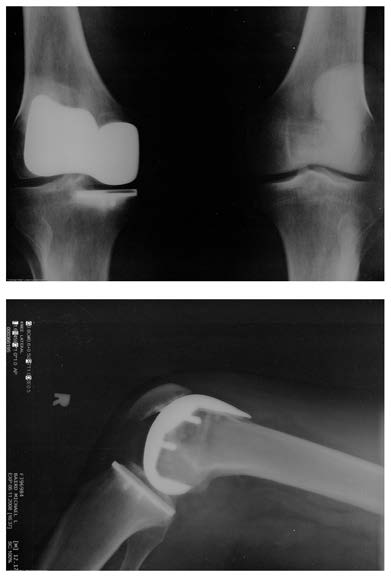

fluid (synovial fluid) that reduces friction and wear. A damaged or arthritic joint can be replaced by an artificial joint (Figure 5.3). These replacements can be made of metals (stainless steel or titanium) or plastic (polyethylene), also with very small coefficients of friction.

Figure 5.3 Artificial knee replacement is a procedure that has been performed for more than 20 years. In this figure, we see the post-op x rays of the right knee joint

replacement. (credit: Mike Baird, Flickr)